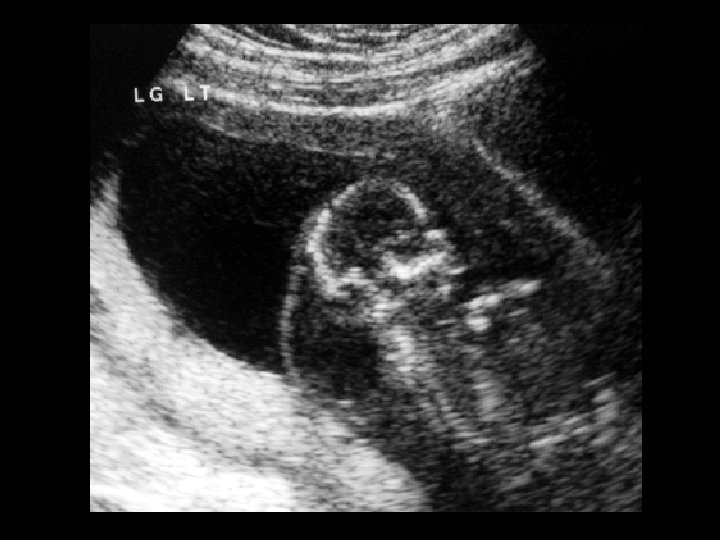

Cystic hygroma • Findings: – 2 nd trimester fetal US shows a large cystic structure along the posterior neck – Recommend amnio • Causes: – Isoloated (nl karyotype) – Generalized hydrops = lymphagiectasia (fatal) – Turner’s / Noonan’s – Trisomy 21, 18, 13